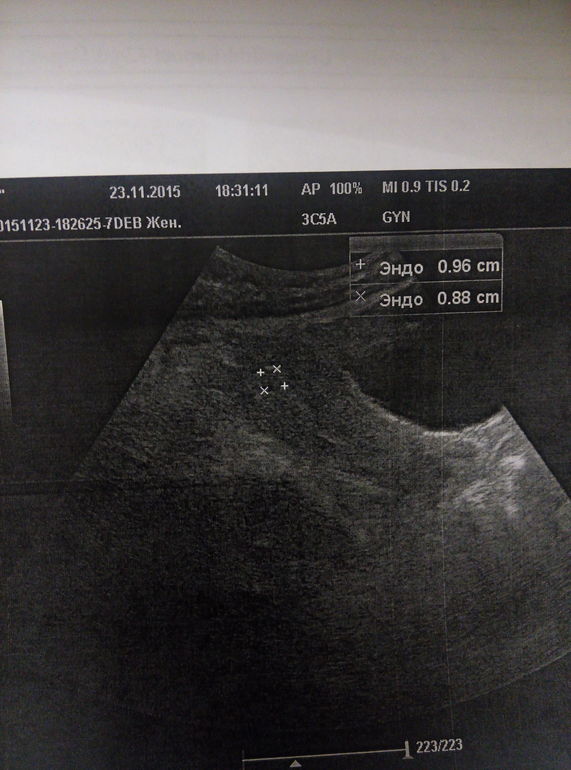

Пока пишу, сыночек проснулся и лениво пересчитывает пяточками мои ребра)))) Какой он уже большой! Даже не верится.. Совсем недавно кажется я видела на экране это:

Потом уже крошечного человечка 8 см длиной: